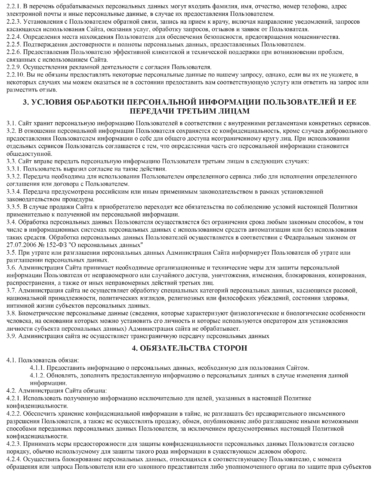

Услуги предоставляются при наличии информированного добровольного согласия Пациента (Законного представителя).

4.5.Ознакомиться и подписать информированное добровольное согласие на медицинское вмешательство, уведомление о последствиях лечения и

рекомендациях.